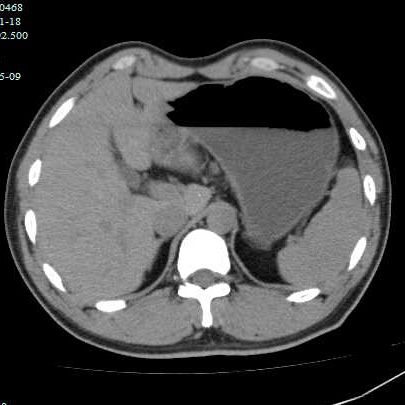

第二个病例,青年男性,也是突然腹痛,症状和第一个类似,首选腹部CT。

因为非影像专业,自己总结肠道植物性结石的特点,混杂密度,多数边缘规则,与正常胃、肠壁结构分界清晰,临床考虑多数急性起病,关键是要问近期是否有大量食用柿子、山楂、黑枣等富含鞣酸食物。